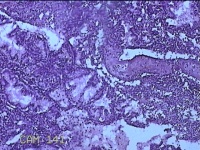

宫颈管组织

性别

女

年龄

33岁

临床诊断

异位妊娠

一般病史

停经52天,阴道流血12天。

标本名称

大体所见

灰白暗红色不规则碎组织4.3x3.3x1.2cm一堆。

图3